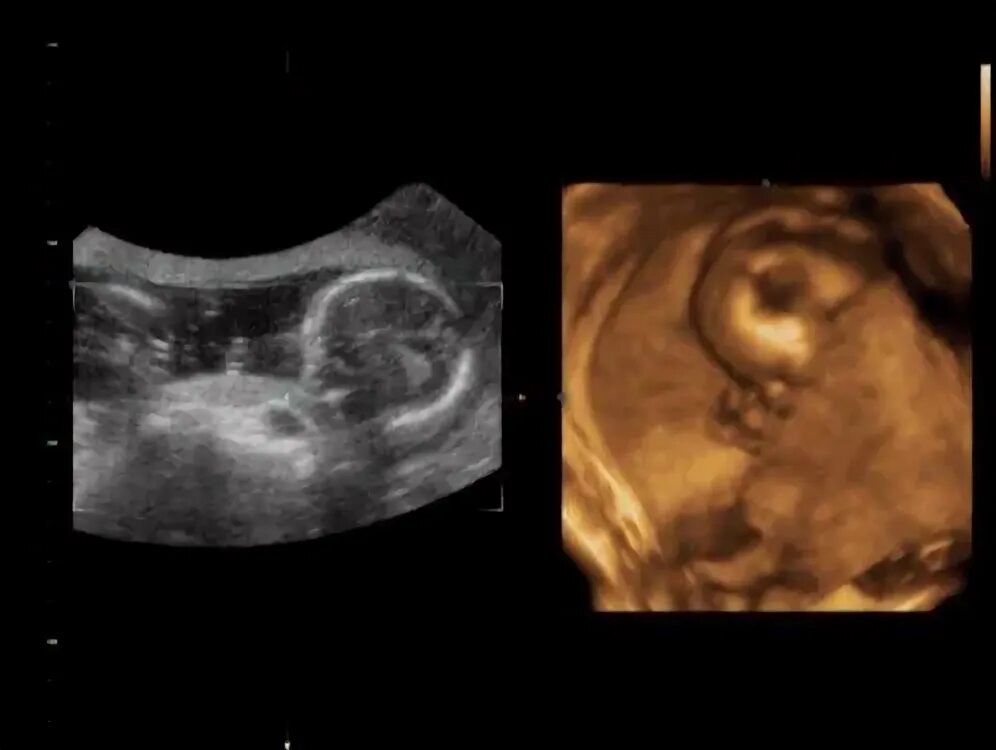

Узи 17 недель девочка